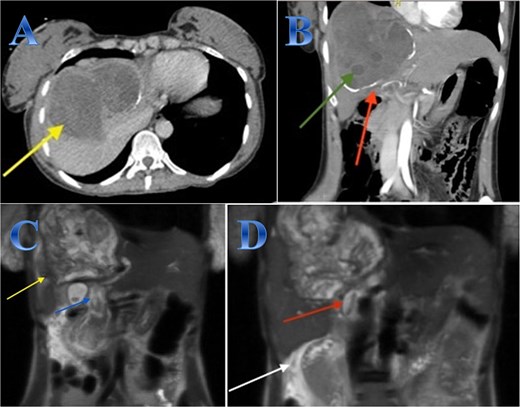

A 35-year-old lady with developed right upper quadrant abdominal pain suddenly. The laboratory tests showed a mild elevation of white blood cells and bilirubin levels. Abdominal US revealed a cystic structure extending from the right to the left hepatic lobes measuring 14 × 5 cm. CT with contrast revealed right hepatic intra-parenchymal cystic lesion with sub-capsular extension (Fig. 2).

Case 2. (A & B) Sagittal and axial CT cuts of the abdomen at venous phase showing right hepatic intra-parenchymal cystic lesion with subcapsular extension with no obvious post contrast enhancement. (C) MRI images showing right hepatic intra-parenchymal cystic lesion with subcapsular extension, proven to be sealed perforation. (D) The intraoperative finding after laparoscopic endocystectomy and the area of the cyst which was occupying the right hemi-liver under the ribs and reaching the diaphragm.

Laparoscopic endocystectomy was recommended. The liver was explored, and the cyst was isolated using gauze soaked in hypertonic saline. A suction device was used to puncture the cyst and aspirate the cyst fluid. Hypertonic saline was injected into the cyst (Fig. 2).